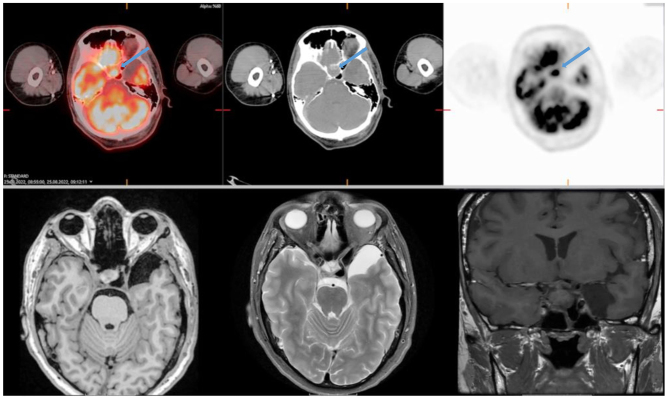

Summary: Primary hypophysitis is a rare disease that may have variable clinical presentations. The main treatment options are clinical observation, immunosuppressive drugs, and surgery. Glucocorticoids are used as first-line medical therapy; however, non-responsiveness and recurrences are the major problems. We present a 30-year-old male patient who had an excellent radiologic response to a single course of glucocorticoids. The patient presented with malaise and severe headaches of acute onset. Cranial MRI revealed a pituitary mass compressing the optic chiasm. Hormonal evaluation studies were consistent with anterior pituitary hormone dysfunction except for the growth hormone axis. There was a mild compression on the optic chiasm in the pituitary MRI. The patient was started on methylprednisolone therapy at a dose of 80 mg/day. The pituitary MRI revealed complete regression of the mass after 2 months, and there was a complete recovery of pituitary functions after 6 months. There is no consensus on the optimal dose and duration of glucocorticoid therapy for primary hypophysitis in the literature. We report that steroid therapy, even in lower doses, might be effective in mild-to-moderate cases.

Learning points: Primary hypophysitis is a rare disease with a varied clinical course, and hence the treatment strategies should be individualized. There is no consensus on the optimal dose and duration of glucocorticoid therapy. Glucocorticoid therapy may induce complete remission in some patients, especially with a mild-to-moderate disease course and during the acute phase of the disease.